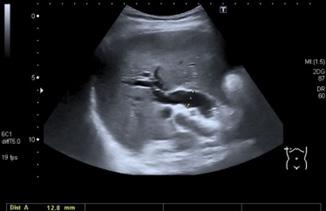

♦ Radiografía baritada: imagen en pico de pájaro o punta de lápiz

Radiología (con bario)

♦ Megaesófago afilado en la punta

♦ Imagen “pico de pájaro”, “punta de lápiz”, “cola de raton”

♦ Nivel hidroaéreo en el mediastino.

♦ Mediastino ensanchado.

Figura 18. Radiología baritada en acalasia. Esófago con imagen en “cola de ratón” o “pico de pájaro”.